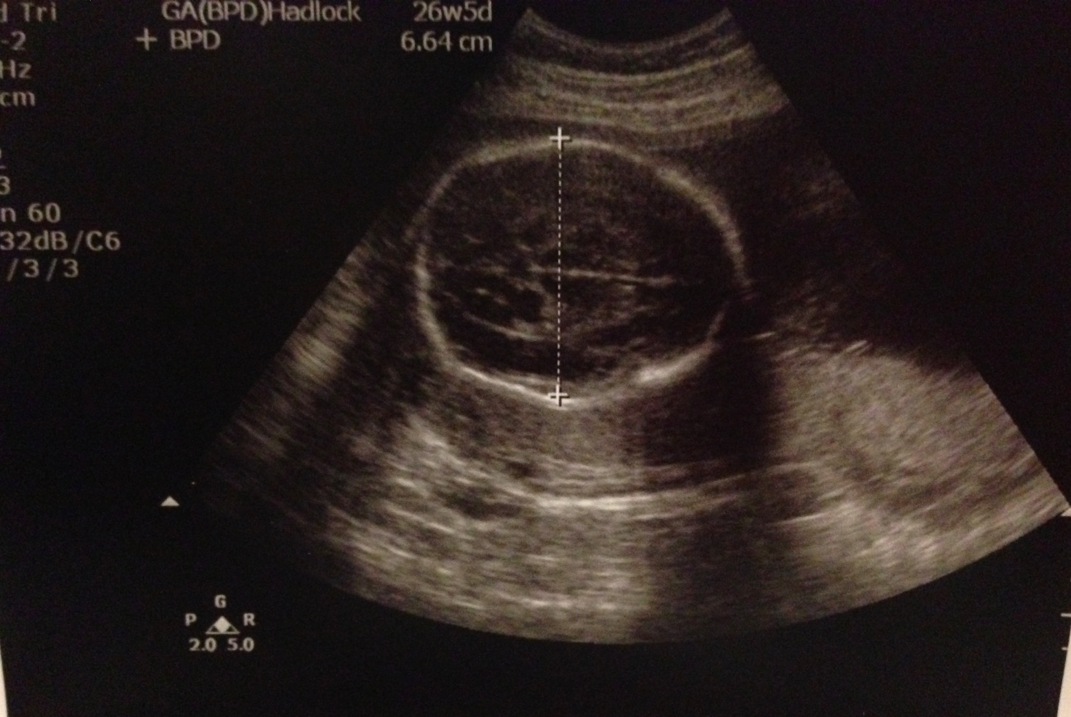

今個星期嘅最新超聲波growth chart﹗頭仔(BPD)反而細了,S醫生話呢個正常丫,其實 閱讀全文